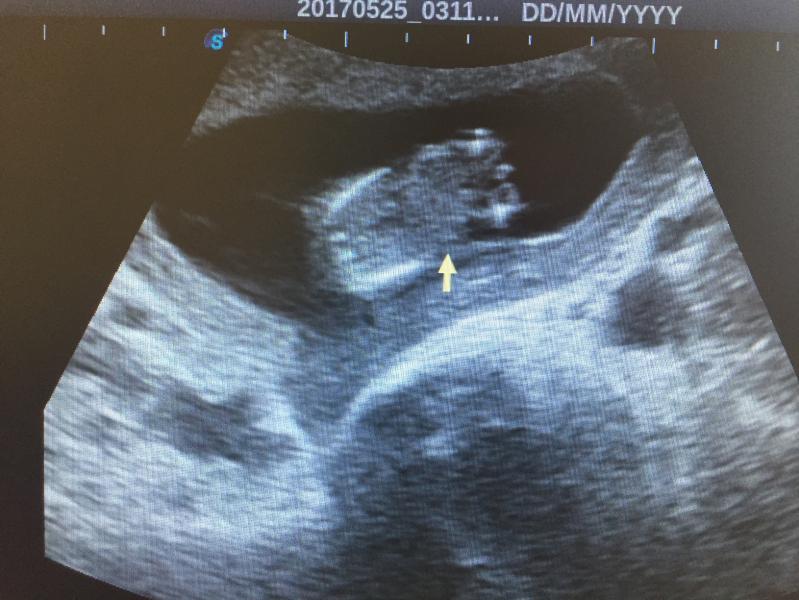

Кому понятно?? на 12нед+6 сделали узи

Сказали мальчик

Справа ножки и будто пипирка между ног)

Попка, ножки и писька?)

Я хоть не понимаю узи но здесь все видно что мальчик машонка видно же.А она говорит что еще рано это не понятный снимок🤨